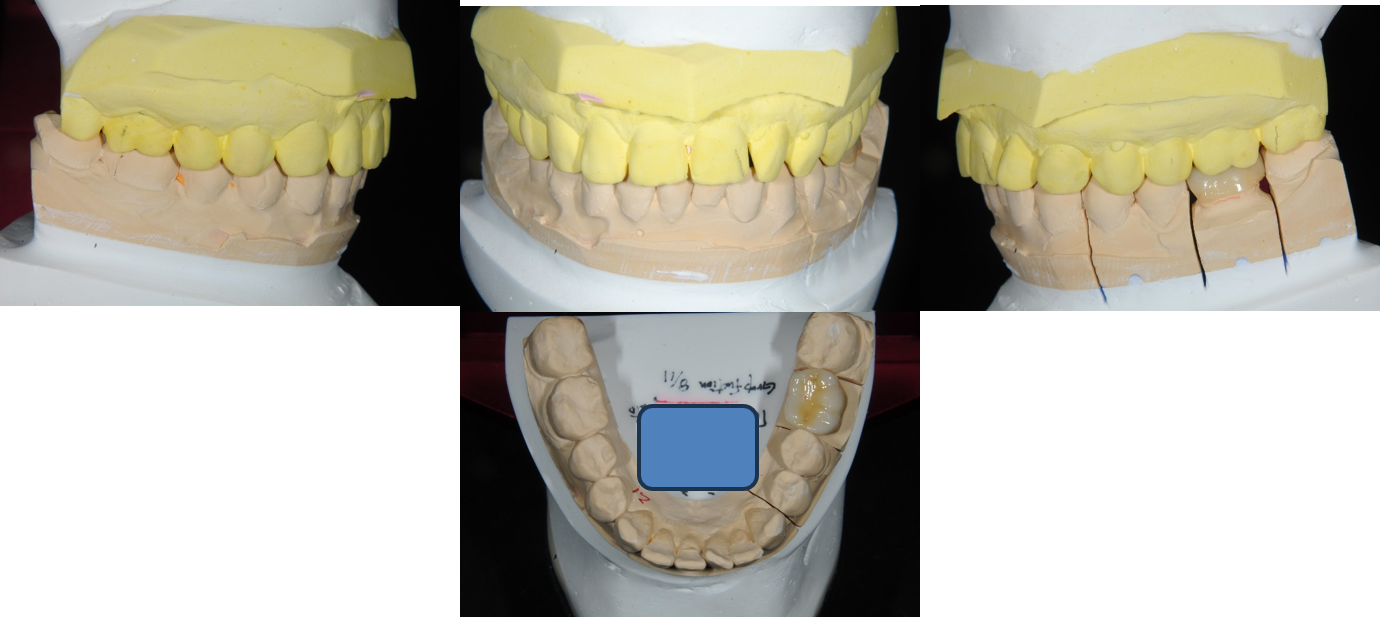

模型上咬合器

咬合器上製作固定假牙